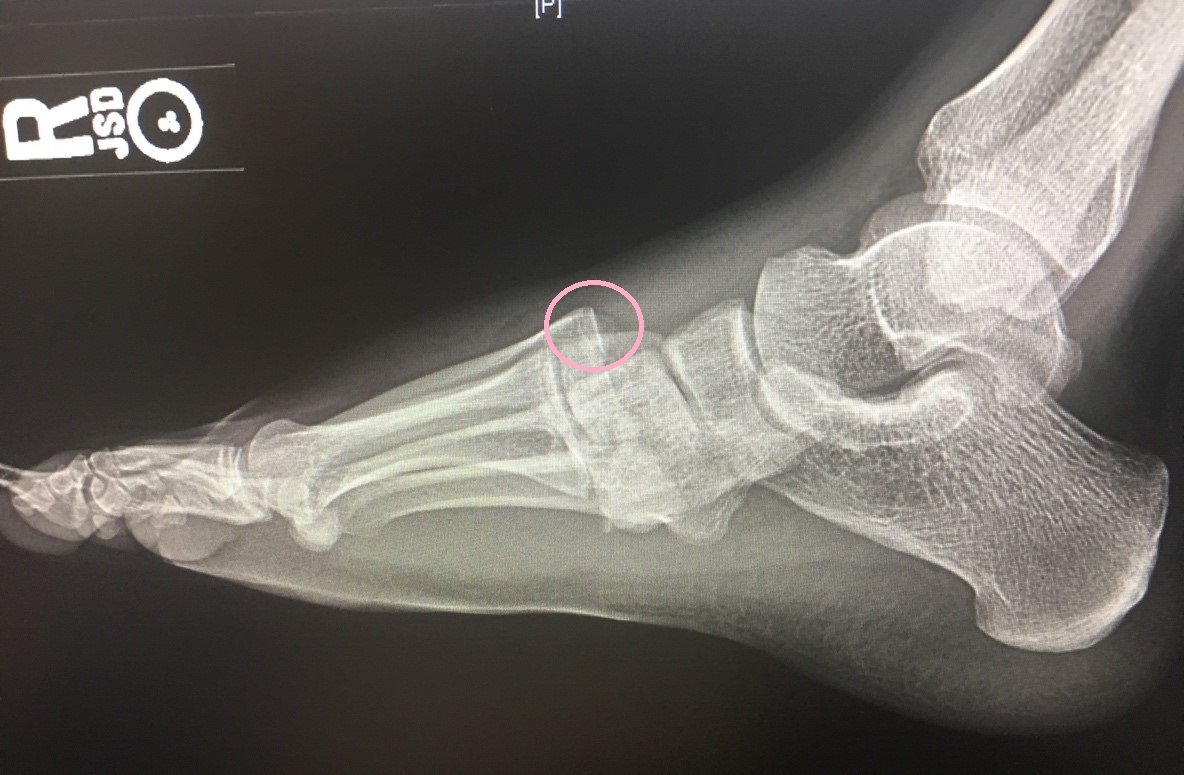

The frontal view of the right foot showed divergent dislocation of the second through fifth metatarsal bones (red outlines) consistent with Lisfranc injury. Though the Lisfranc ligament is not visualized by radiograph, the yellow markings represent the location of the Lisfranc ligament between the medial cuneiform (blue dot) and the base of the second metatarsal bone. The first metatarsal and the medial cuneiform remain congruent. The lateral view shows dorsal dislocation of the midfoot (pink circle) consistent with instability. There is associated extensive midfoot soft tissue swelling.